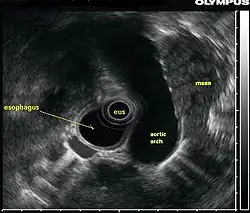

Эндосоногра́фия (эндоскопи́ческий ультразву́к) — комбинированное исследование, при котором ультразвуковой датчик с помощью эндоскопа вводится в полость пищевода, желудка или кишечника с целью получить более чёткие изображения глубоко расположенных органов.[1] Может сочетаться с допплерографией для оценки кровотока в сосудах, а также с тонкоигольной аспирационной биопсией[2].

Благодаря высокой частоте (5—20 МГц) ультразвука повышается разрешающая способность исследования, что позволяет различить структуры стенки кишки и прилегающих органов на расстоянии 4—6 см, а также патологические образования малых размеров[1].